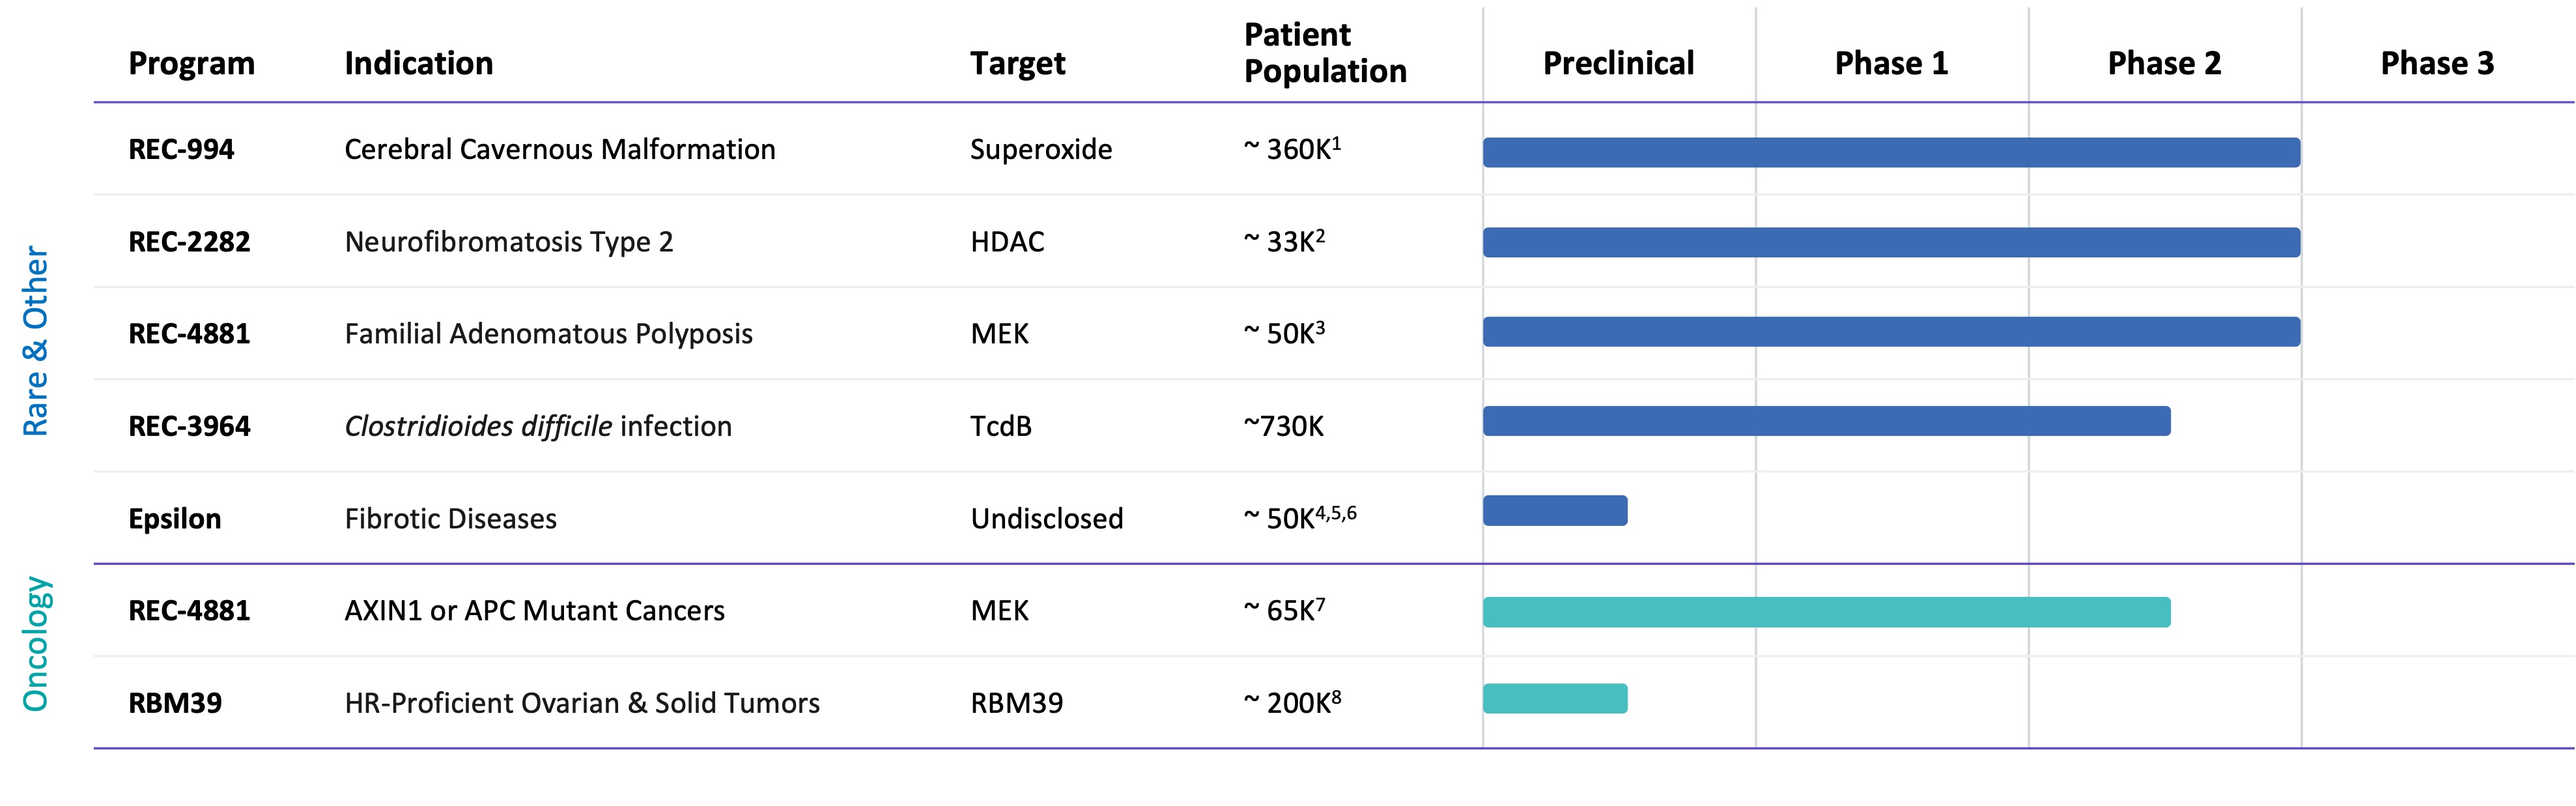

Pipeline

•Five phase 2 clinical-stage programs with multiple upcoming data readouts expected, including REC-994 in cerebral cavernous malformation (CCM) in Q3 2024, REC-2282 in neurofibromatosis type 2 (NF2) in Q4 2024, REC-4881 in familial adenomatous polyposis (FAP) in H1 2025, and REC-4881 in AXIN1 or APC mutant solid tumors in H1 2025

•Completed a Phase 1 study for REC-3964 in healthy volunteers for the potential treatment of Clostridioides difficile (C. difficile) infection with a favorable safety and tolerability profile

•Advanced our RBM39 program in homologous recombination proficient ovarian cancer and other solid tumors to IND-enabling studies

•In-licensed a program (Target Epsilon) that emerged from our fibrosis collaboration with Bayer that represents a novel approach to treating fibrotic diseases with compelling early data